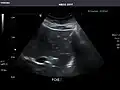

Abdominal Ultrasound (Full Exam)

STRUCTURED REPORT

(Technique: Transabdominal ultrasonography; Device: Toshiba Aplio XG)

Liver: Diffusely homogeneous and normal in echogenicity. No focal mass or contour nodularity. No intrahepatic biliary ductal dilatation.

Portal Vein: Patent main portal vein.

Gallbladder: No stones, wall thickening, or pericholecystic fluid.

Common Bile Duct: Nondilated measuring 1.3 mm at the level of the porta hepatis.

Pancreas: Visualized portions unremarkable.

Spleen: Normal in size.

Kidneys: Right and left kidneys measure 11.5 cm and 12 cm in length respectively. No hydronephrosis. Small left lower pole kidney cyst.

Ascites: None.

Aorta: Visualized portions normal in caliber, 16 x 15 mm.

IVC: Normal.

IMPRESSION:

Normal abdominal ultrasound.

Spleen -